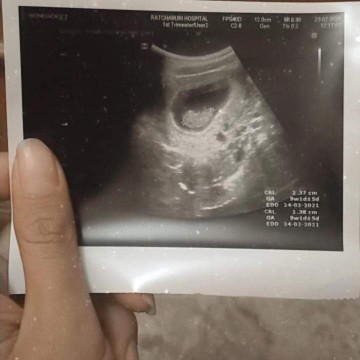

ซาวด์ครั้งแรกท้อง11วีคก้เจอแบบนี้เรยค่ะเสียใจกังวลมากค่ะอีก2อาทิตย์หมอนัดอีกเรายังมีหวังที่จะเจอตัวน้องยุไหมคะสอบถามแม่ๆที่เจอเรื่องแบบนี้หน่อยค่ะขอบคุณสำหรับคำตอบค่ะ😔

ของเรา11wค่ะ น้องเป็นตัวแล้ว